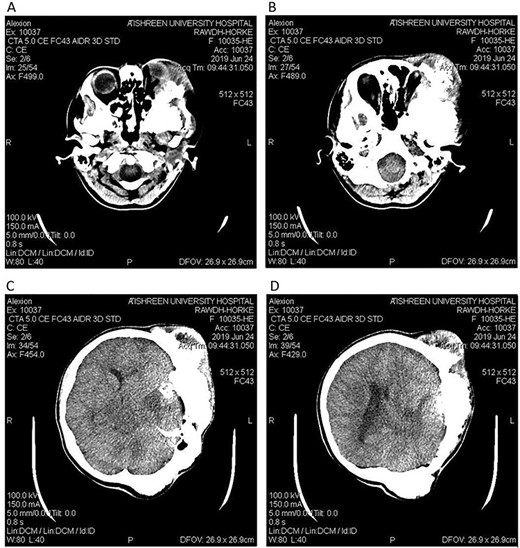

Postoperative CT head bone window (A–C). A. Regression of the pressure on the maxillary sinus. B. Decline of the exophthalmos. C. The parietal bone after excision of the masses. Tissue window (D). Regression of the pressure on left lateral ventricle and decline of the midline shift.

A 17-year-old female presented with a history of osteosarcoma that was confirmed after undergoing a surgery to remove an enlarging bone tumor in the left temporal region 2 years ago. She later got pregnant and delivered her child but never got back for a checkup until she was admitted to our hospital with a severe and unresponsive to medication headache that progressed over the course of 6 months and blurred vision that progressed to complete left-sided vision loss. Physical examination revealed a tough and mobile yet fixed at the base 7-cm mass towards the left of the frontal bone. Many more masses were revealed in the left side of the skull including the anterior cranial fossa, orbit, base of the skull and the left part of the occipital region where the previous procedure was performed (Fig. 1). These masses had been increasing in size probably under the influence of pregnancy hormones causing pain that radiated along the orbital and maxillary branches of the left trigeminal nerve. Physical examination and past medical history were otherwise unremarkable. Laboratory tests were all normal, and her family history was negative. Staging studies showed no evidence of distant metastatic disease in the chest, the abdomen and the pelvis. CT scan of the skull revealed a bone-forming non-lytic lesion accompanied by periosteal reaction. This lesion bulges to the outside towards the scalp spreading into both the soft tissues and the inside of the entire left side of the skull with a sunburst-pattern (Figs 2 and 3). Its rims are unsymmetrical and pointy, and it bulges into the left orbit outside the muscles causing exophthalmos with a semi-complete proptosis of the eyeball out of the orbit (Figs 2 and 3). This lesion applies pressure to the left frontal and temporal lobes causing mild edema in both these lobes without invading the brain tissue. This edema in turn applies pressure to the left lateral ventricles (minor shift of the elements of the midline to the right side can be seen on CT) (Fig. 4). Due to the tumor’s wide spread, the surgical procedure was performed in two stages (approximately 6-hour-long each). In the first stage, the bone mass was removed through a procedure of wide skull approach including the frontal, temporal and parietal bones and a removal of the invading part of the temporal muscle. Moreover, the lateral wall and roof of the left orbit were removed, the left optic nerve was dissected free and part of the meninges was removed and replaced with an autogenic patch from the fascia lata. Then, the bone loss was compensated for by using bone cement Synicem VTP (poly methyl methacrylate and Barium sulfate), and the orbit was rebuilt; the eyeball was placed back with noticeable decline of the exophthalmos. In the second stage, a complementary left parietal occipital incision of the previous approach was performed 3 weeks later; the remaining of the frontal and occipital bones was removed, and a partial mastoid surgery was done. Furthermore, the cavernous sinus were revealed and found to be not invaded. Later on, the normal skull shape was restored using the same cement. The histopathology of the lesion revealed proliferation of neoplastic chondroblasts, osteoblasts and spindle-shaped cells. The features are consistent with low-grade chondroblastic osteosarcoma (Fig. 5). The patient did not need ICU admission. She recovered well 3 days after the surgery and was discharged with no deficits. A CT scan that was performed post-operatively revealed that the masses were successfully excised (Figs 6 and 7). At the last follow-up 1 month post-operation, the patient was scheduled to undergo a course of radiotherapy, 60 Gy of radiotherapy in 30 fractions over 4 weeks without chemotherapy, as it is not recommended with low-grade osteosarcoma.